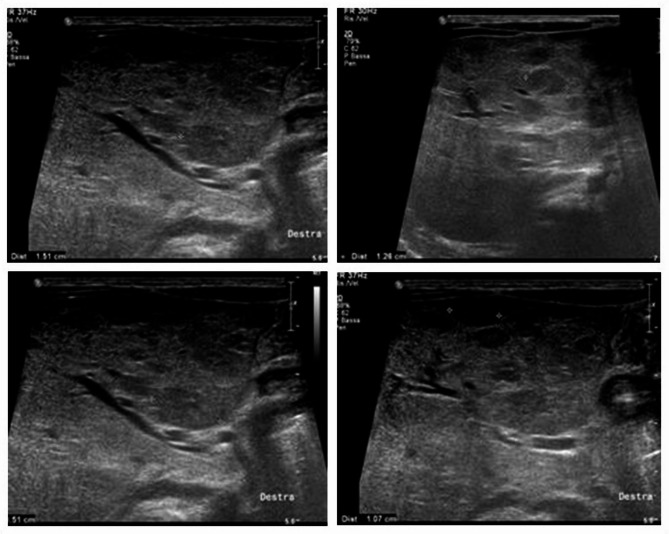

Consumptive hypothyroidism complicating infantile hepatic hemangioma successfully treated with propranolol: a case report and literature review.

普萘洛尔成功治疗小儿肝血管瘤消耗性甲状腺功能减退1例并文献复习。